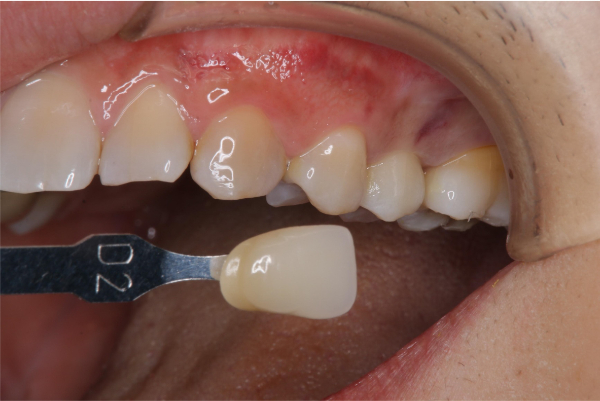

比色照相

術前、術後比較